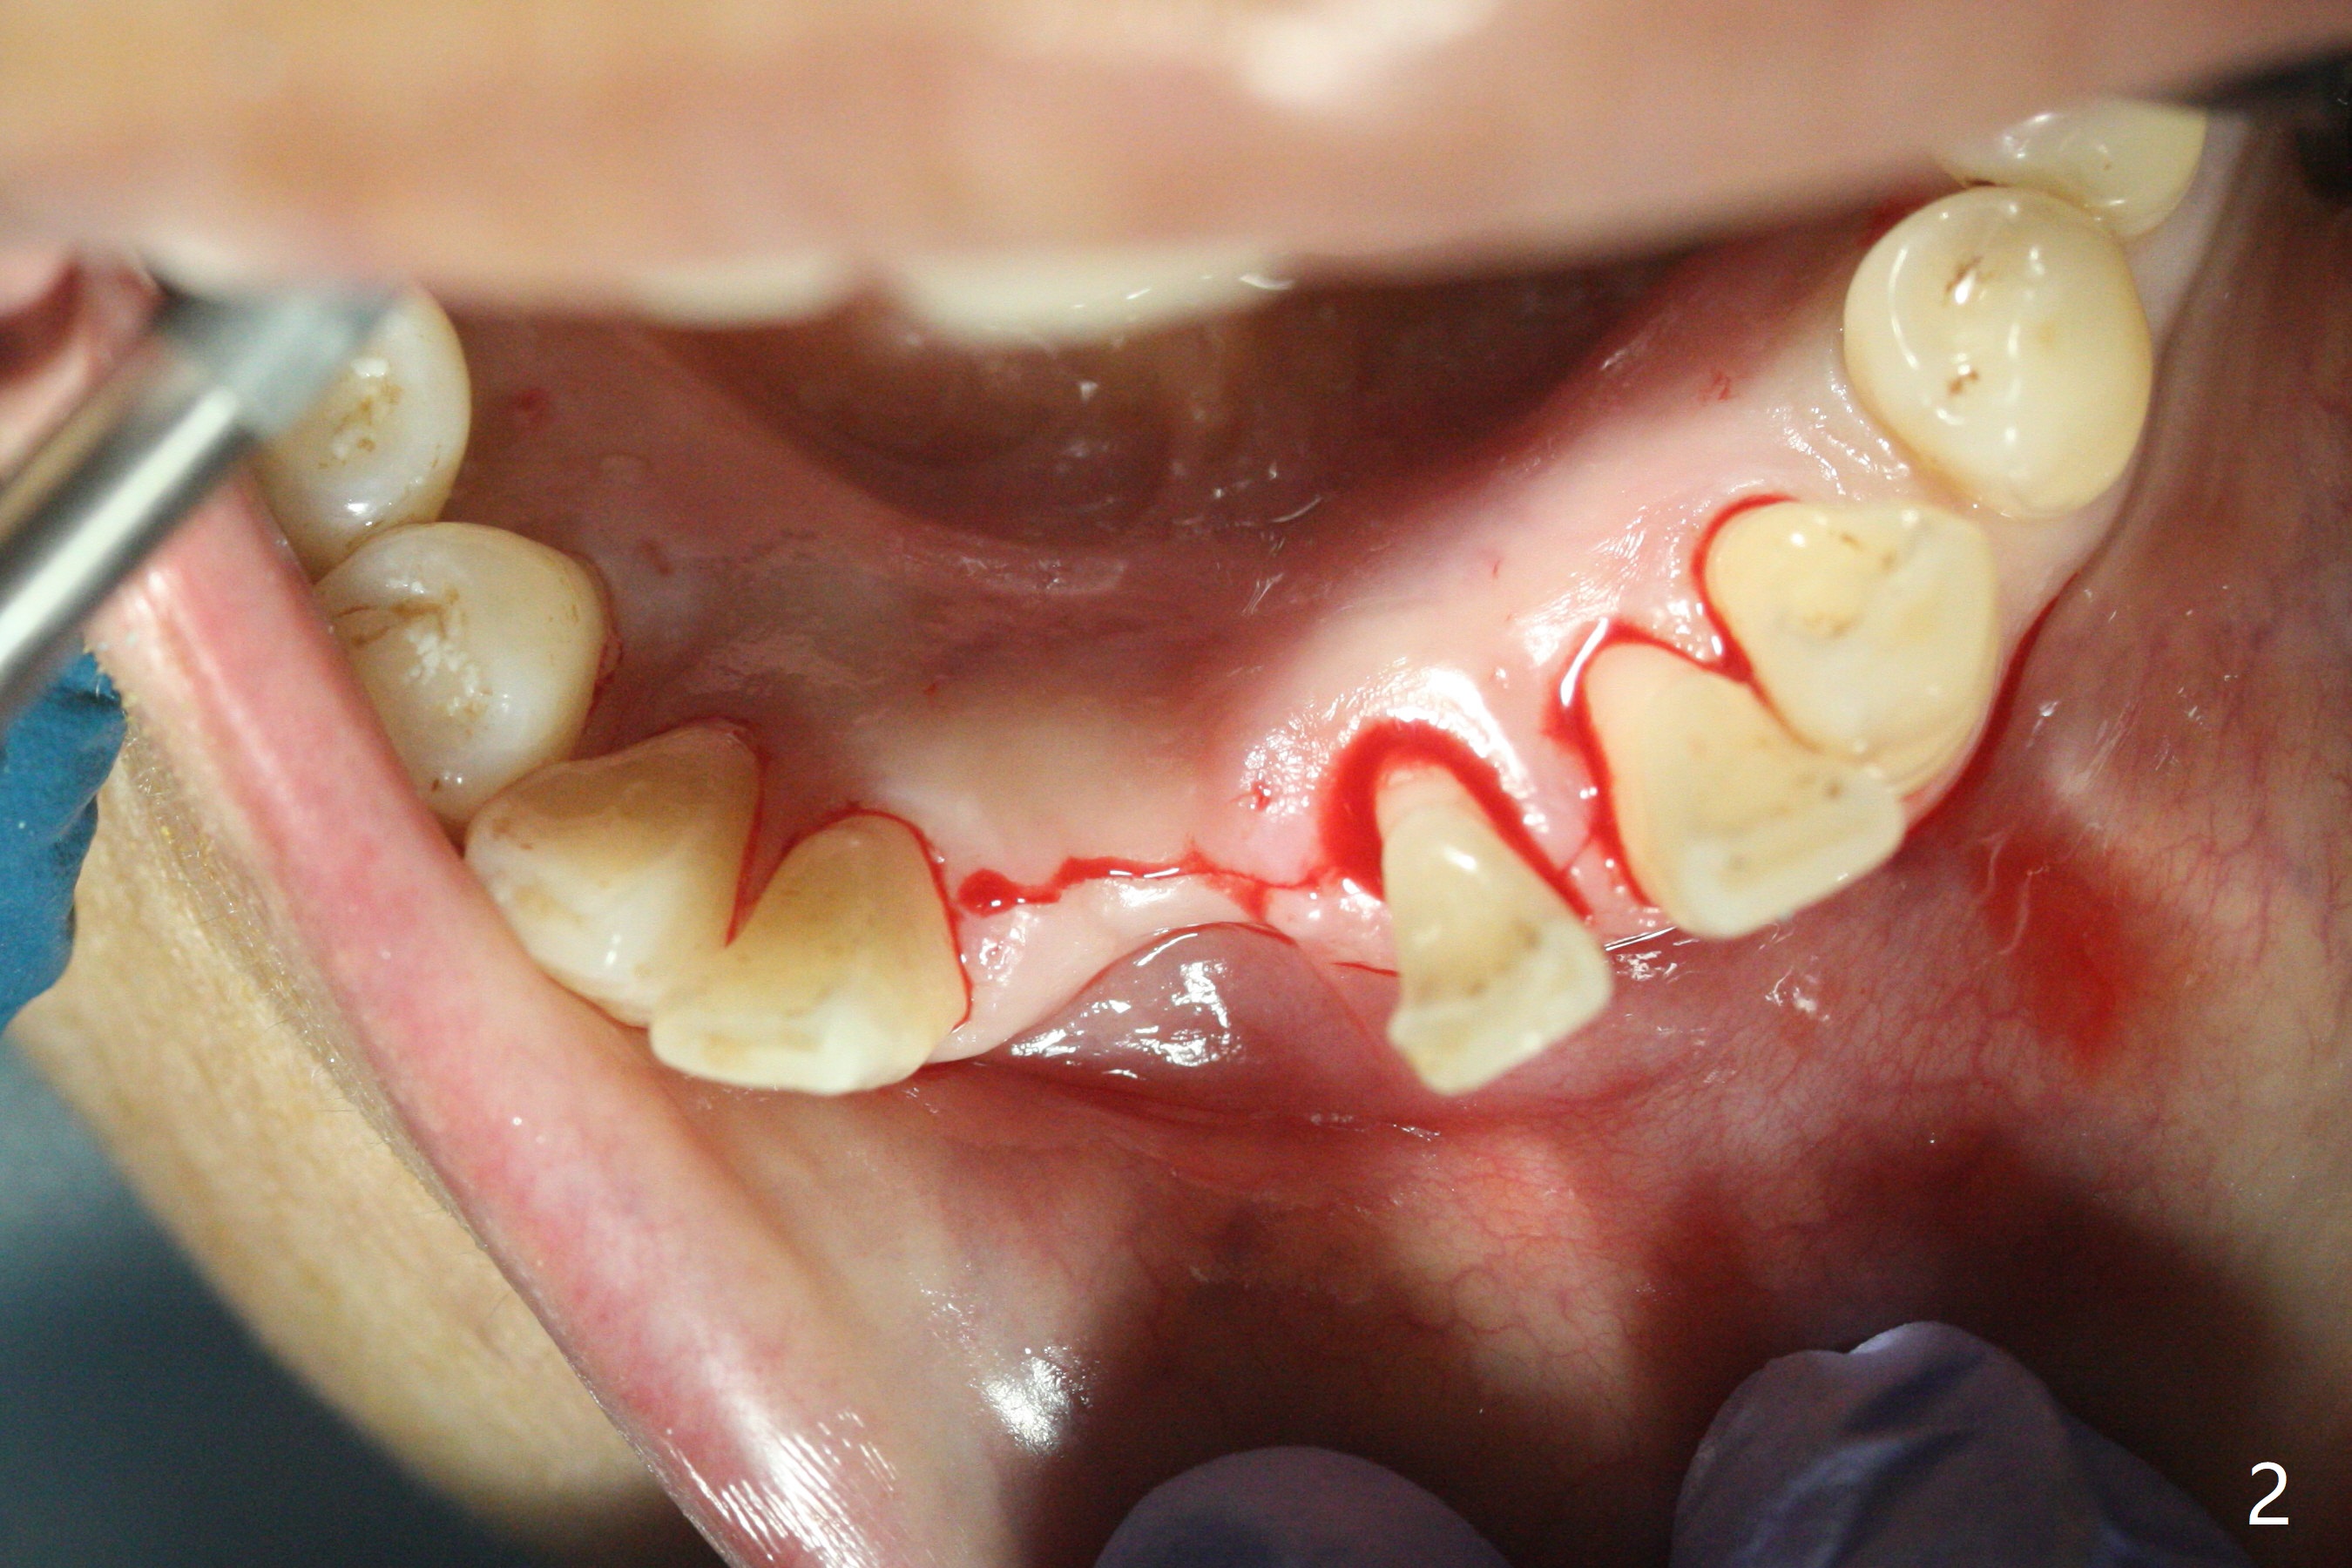

56岁女十分恐惧治疗,缺失右下1,其余切牙由于骨质吸收颊侧移位(图一:1,2),但是她不愿意拔除,同意右下1种植,牙周骨手术,植骨;植体整合后作为支抗,矫正移位下门牙。为了防止忘记舌侧瓣分离,先做舌侧切口(图二),然后颊侧瓣松弛分离(图三),包括使用前牙隧道刀(图四)切断颊侧骨膜,松弛到颊侧瓣能向舌侧牵拉3-4毫米(图五),舌侧瓣骨膜下广泛,深部分离(好像不能切断骨膜,图六),放置导板,磨平狭窄的牙槽嵴(图七:O(osteotomy)),植入2.5x12(4)毫米一段式植体(图八:故意舌侧植入,以便以后矫正),在颊侧骨板打多个出血洞(图八:箭头),然后把在平的器皿上形成的粘性骨板(sticky bone,图九),放置于植体和移位切牙周围(图十),接着使用消毒过的橡皮障punch(图十一(纸头相当于PRF膜;事先给助手示范))在三个PRF膜(图十二)打洞,套在植体和门牙上(图十三: 箭头),防止膜(图十四)和骨块(图十五,十六:*)移位,最后还必须使用最原始方法牙周敷料保护伤口(图十七)。术后9天,舌侧牙周敷料脱落,伤口稍微裂开(图十八)。术后18天撤除敷料,伤口裂开处有新鲜肉芽组织生长(图十九(*:下面是填入的骨粉,将是增宽的牙槽嵴(如果你是乐观主义者)),二十)。病人十分感激我们帮助她度过难关。她的确有sleep apnea,否定tongue thrust。术后三个月植体周围没有明显骨质吸收(图二十一至二十三),左下1,2轻度反合(图二十四),植体周围软组织健康(图二十五),5-5安置矫正器(图二十六,二十七,12 niti)。一周后下切牙向舌侧移动(图二十八),左下1,2反合纠正(图二十九)。再一周变化不大(图三十),植牙圈有些松动,两周后将重做临时牙冠,槽往舌侧移动。结果病人提前回来,植牙槽舌侧移位。一周后右下2不适(图三十一),尝试近中牵引(图三十二)。